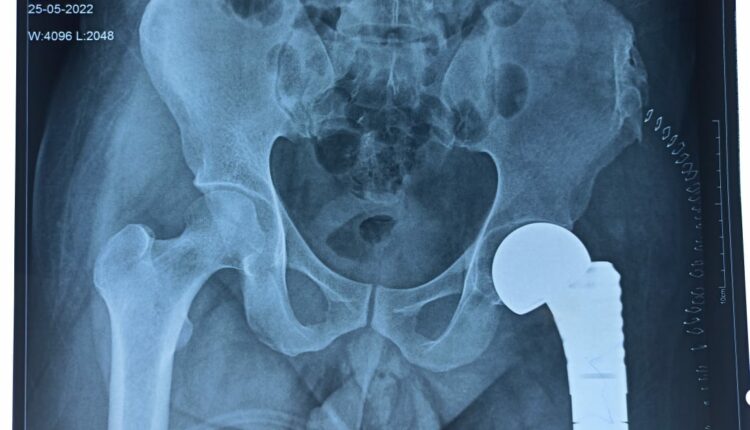

ଏହି ଯୁବକଙ୍କ ବାମ ଜଙ୍ଘହାଡ଼ରେ ଏକ ବଡ଼ ଟ୍ୟୁମର ରହିଥିଲା। ଉକ୍ତ ଯୁବକ ଜଣଙ୍କ ଜଙ୍ଘହାଡ଼ରେ ପ୍ରିମିଟିଭ ନ୍ୟୁରୋଏକ୍ଟୋଡର୍ମାଲ୍ ଭଳି ଜଟିଳ ରୋଗରେ ପୀଡ଼ିତ ଥିଲେ। ଏନେଇ ସେ ପୂର୍ବରୁ ୨୦୧୮ ଏବଂ ୨୦୧୯ରେ ଦୁଇ ଦୁଇଟି ଅସ୍ତ୍ରୋପଚାର କରିସାରିଥିଲେ। ମାତ୍ର ତାହା ଟ୍ୟୁମରକୁ ସମ୍ପୂର୍ଣ୍ଣରୂପେ ହଟାଇବା ପାଇଁ ପର୍ଯ୍ୟାପ୍ତ ନଥିଲା। ପରବର୍ତ୍ତୀ ସମୟରେ ଯୁବକଙ୍କ ଠାରେ ଉକ୍ତ ଟ୍ୟୁମର ବୃଦ୍ଧି ପାଇବା ସହିତ ଅସହ୍ୟ ପୀଡ଼ା ଅନୁଭୂତ ହୋଇଥିଲା। ତେଣୁ ଏହି ଅସ୍ତ୍ରୋପଚାର ପୂର୍ବରୁ ତାଙ୍କୁ କେମୋଥେରାପି ଦିଆଯାଉଥିଲା। ଉକ୍ତ ବିପଦପୂର୍ଣ୍ଣ ଟ୍ୟୁମରଟି ରକ୍ତବାହି ପାଖାପାଖି ଥିଲା। ତେଣୁ ଅତ୍ୟନ୍ତ ସତର୍କତା ଓ ଯତ୍ନର ସହିତ ଅସ୍ତ୍ରୋପଚାର କରାଯାଇ ସମ୍ପୂର୍ଣ୍ଣ ଟ୍ୟୁମରଟିକୁ ଟୋଟୋରେ ଏକ୍ସାଇଜ୍ କରାଯାଇ ସମ୍ପୂର୍ଣ୍ଣ ଜଙ୍ଘହାଡ଼ ପ୍ରତିରୋପଣ କରାଯାଇଥିଲା।

ଅସ୍ଥିଶଲ୍ୟ ବିଭାଗର ଡ. ସୁଜିତ କୁମାର ତ୍ରିପାଠୀ ଏବଂ ତାଙ୍କ ଟିମ ଦ୍ୱାରା ଏହି ଜଟିଳ ମେଗାପ୍ରୋଥେସିସ୍ ପ୍ରତିରୋପଣ କରାଯାଇଥିଲା। ଏହି କଠିନ ଅସ୍ତ୍ରୋପଚାର ପ୍ରାୟ ୪ ଘଣ୍ଟା ସମୟ ନେଇଥିଲା | ଡ. ଅପରାଜିତା ପଣ୍ଡା ଏବଂ ତାଙ୍କ ଦଳ ଅସ୍ତ୍ରୋପଚାରରେ ନିଶ୍ଚେତକ ଯୋଗାଇ ଦେଇଥିଲେ। ରାଜ୍ୟରେ ଏପରି ସମ୍ପୂର୍ଣ୍ଣ ଜଙ୍ଘହାଡ଼ ପ୍ରତିରୋପଣ ପ୍ରଥମଥର ପାଇଁ ହୋଇଛି।